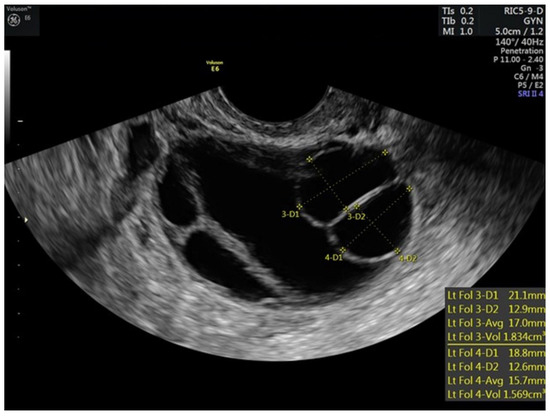

| 7 | 5 | 40 | 100 | 75 | 250 | 84 | 12,11,10,9,9,7 | 12,12,11,10,9,8 | 4.7 | |||

| 8–9 | 5 | 40 | 100 | 75 | 250 | 116 | 15,14,13,11,10,9 | 16,14,13,13,12,7 | 5.8 | |||

| 10 | 5 | 40 | 100 | 75 | 250 | 172 | 0.6 | 19,17,17,13,12,12,9,6 | 18,17,16,16,13,4 | 5.3 | ||